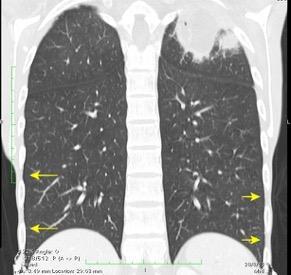

Derrame pleural..33,3% Derrame bilateral.26,7% Ganglios mediastínicos e hiliares..66,7%..

No hiliares

Okada F et al. Chest HRCT findings in acute transformation of adult T-cell lymphoma/leukemia. Eur Radiol 2015

Vidrio deslustrado 60%. Consolidación 33,3% Nódulos…33,3%